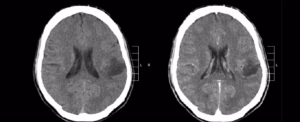

Пацієнти з гліобластомою, найбільш смертельним видом пухлини мозку у дорослих, відчувають особливо різке зниження якості життя. Вважається, що гліобластоми порушують нормальні функції мозку , стискаючи та викликаючи набряк здорових тканин або конкуруючи з ними за кровопостачання.

Щоб вивчити, як гліобластоми взаємодіють з нейронними ланцюгами в мозку людини, ми реєстрували мозкову активність пацієнтів із гліомами в реальному часі, коли їм показували фотографії звичайних об’єктів або тварин і просили назвати, що вони зображували під час операції на мозку для видалення пухлини.

Поки пацієнти виконували ці завдання, мовні мережі в їхньому мозку були активовані, як і очікувалося. Однак ми виявили, що ділянки мозку, в які пухлини проникли досить віддалено від відомих мовних зон мозку, також активувалися під час виконання цих завдань.

Це несподіване відкриття показує, що пухлини можуть захоплювати та реструктурувати зв’язки в тканині мозку, що їх оточує, і підвищувати їх активність.

Це може пояснити зниження когнітивних функцій, яке часто пов’язане з прогресуванням гліом. Проте, безпосередньо реєструючи електричну активність мозку за допомогою електрокортикографії , ми показали, що, попри гіперактивність, ці віддалені ділянки мозку значно зменшили обчислювальну потужність.